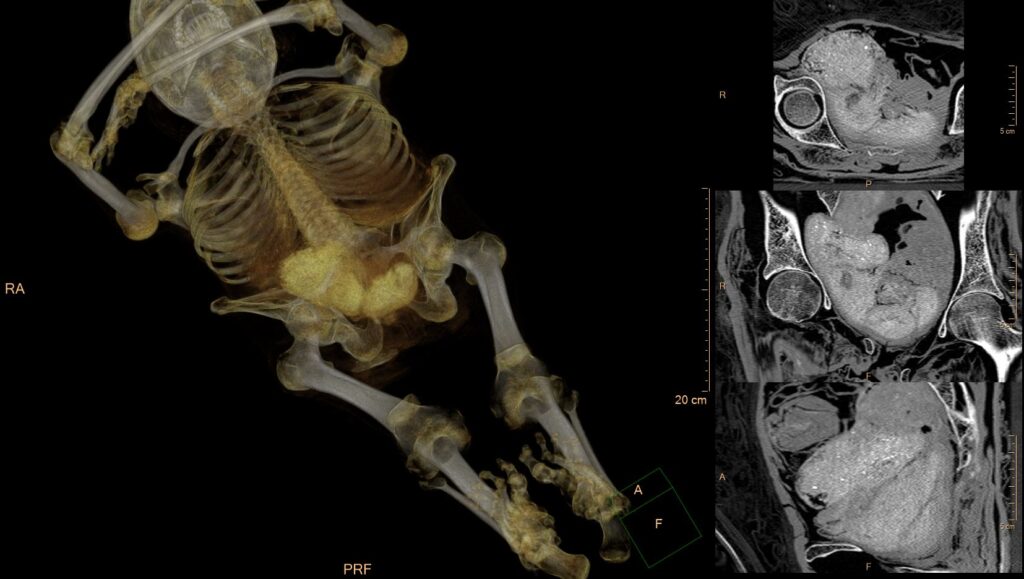

Zestaw obiektów w miednicy mumii interpretowany jako rzekomy płód. Rekonstrukcja 3D całej mumii oraz zrekonstruowane przekroje 2D przez miednicę i pakunki. TK i postprocessing: dr Ł. Kownacki